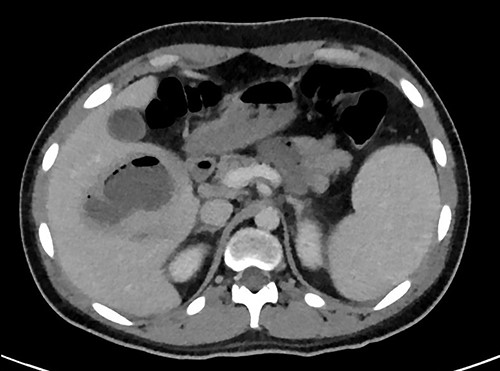

A full lab panel was ordered and revealed a total bilirubin of 1.1, direct bilirubin 0.5, lactate dehydrogenase 196, alkaline phosphatase 80, aspartate transaminase 46 and alanine transaminase 58. A computed tomography (CT) angiographic scan of the chest, abdomen and pelvis revealed the presence of a rim enhancing fluid collection in hepatic segment V with internal gas and containing a metallic foreign body, measuring 8 × 5 cm and consistent with abscess formation (Figs 2–4). The linear tract of the bullet in the right iliac crest was visualized in the CT as well.

Transverse plane of the CT showing the hepatic collection measuring 8 × 5 cm.